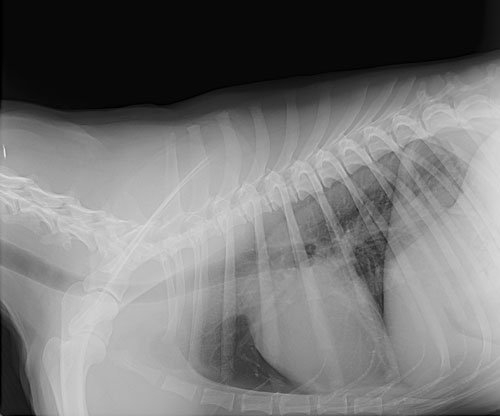

Radiographs can be used to diagnose fractured bones, intestinal foreign bodies, bladder stones, and can be a useful tool in cardiac disease. Ultrasound imaging can be used for looking at internal organs such as the liver and kidneys, assessing an animal for pregnancy, or diagnosing abdominal tumors. We have a brand new, state-of-the-art Ultrasound machine to provide your pet with the most up-to-date care.